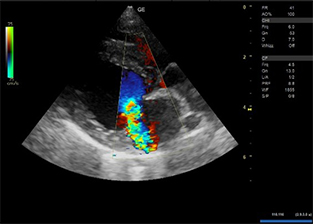

明らかな腹水貯留は認められなかった。 - 心エコー図検査にて、僧帽弁の逸脱とそれに伴う僧帽弁逆流が認められた。